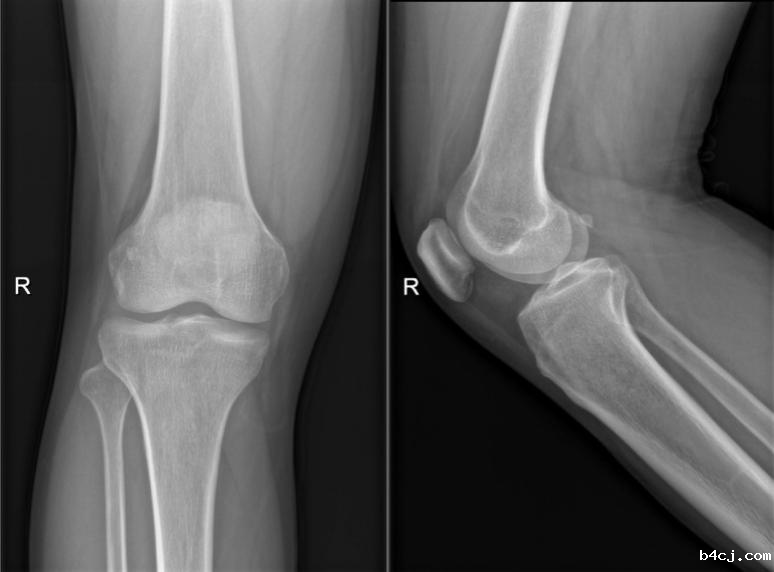

走路也会骨折么?会的。近日,40岁的张先生,自觉双膝疼痛半个月,起初并没在意,可随着日常走路疼痛逐渐加重,于是前来我院放射科拍了X光片(图1),但是并未发现异常,于是又听从医生的建议进行了膝关节的磁共振检查(图2)。最后的诊断结果为应力性骨折。

图1